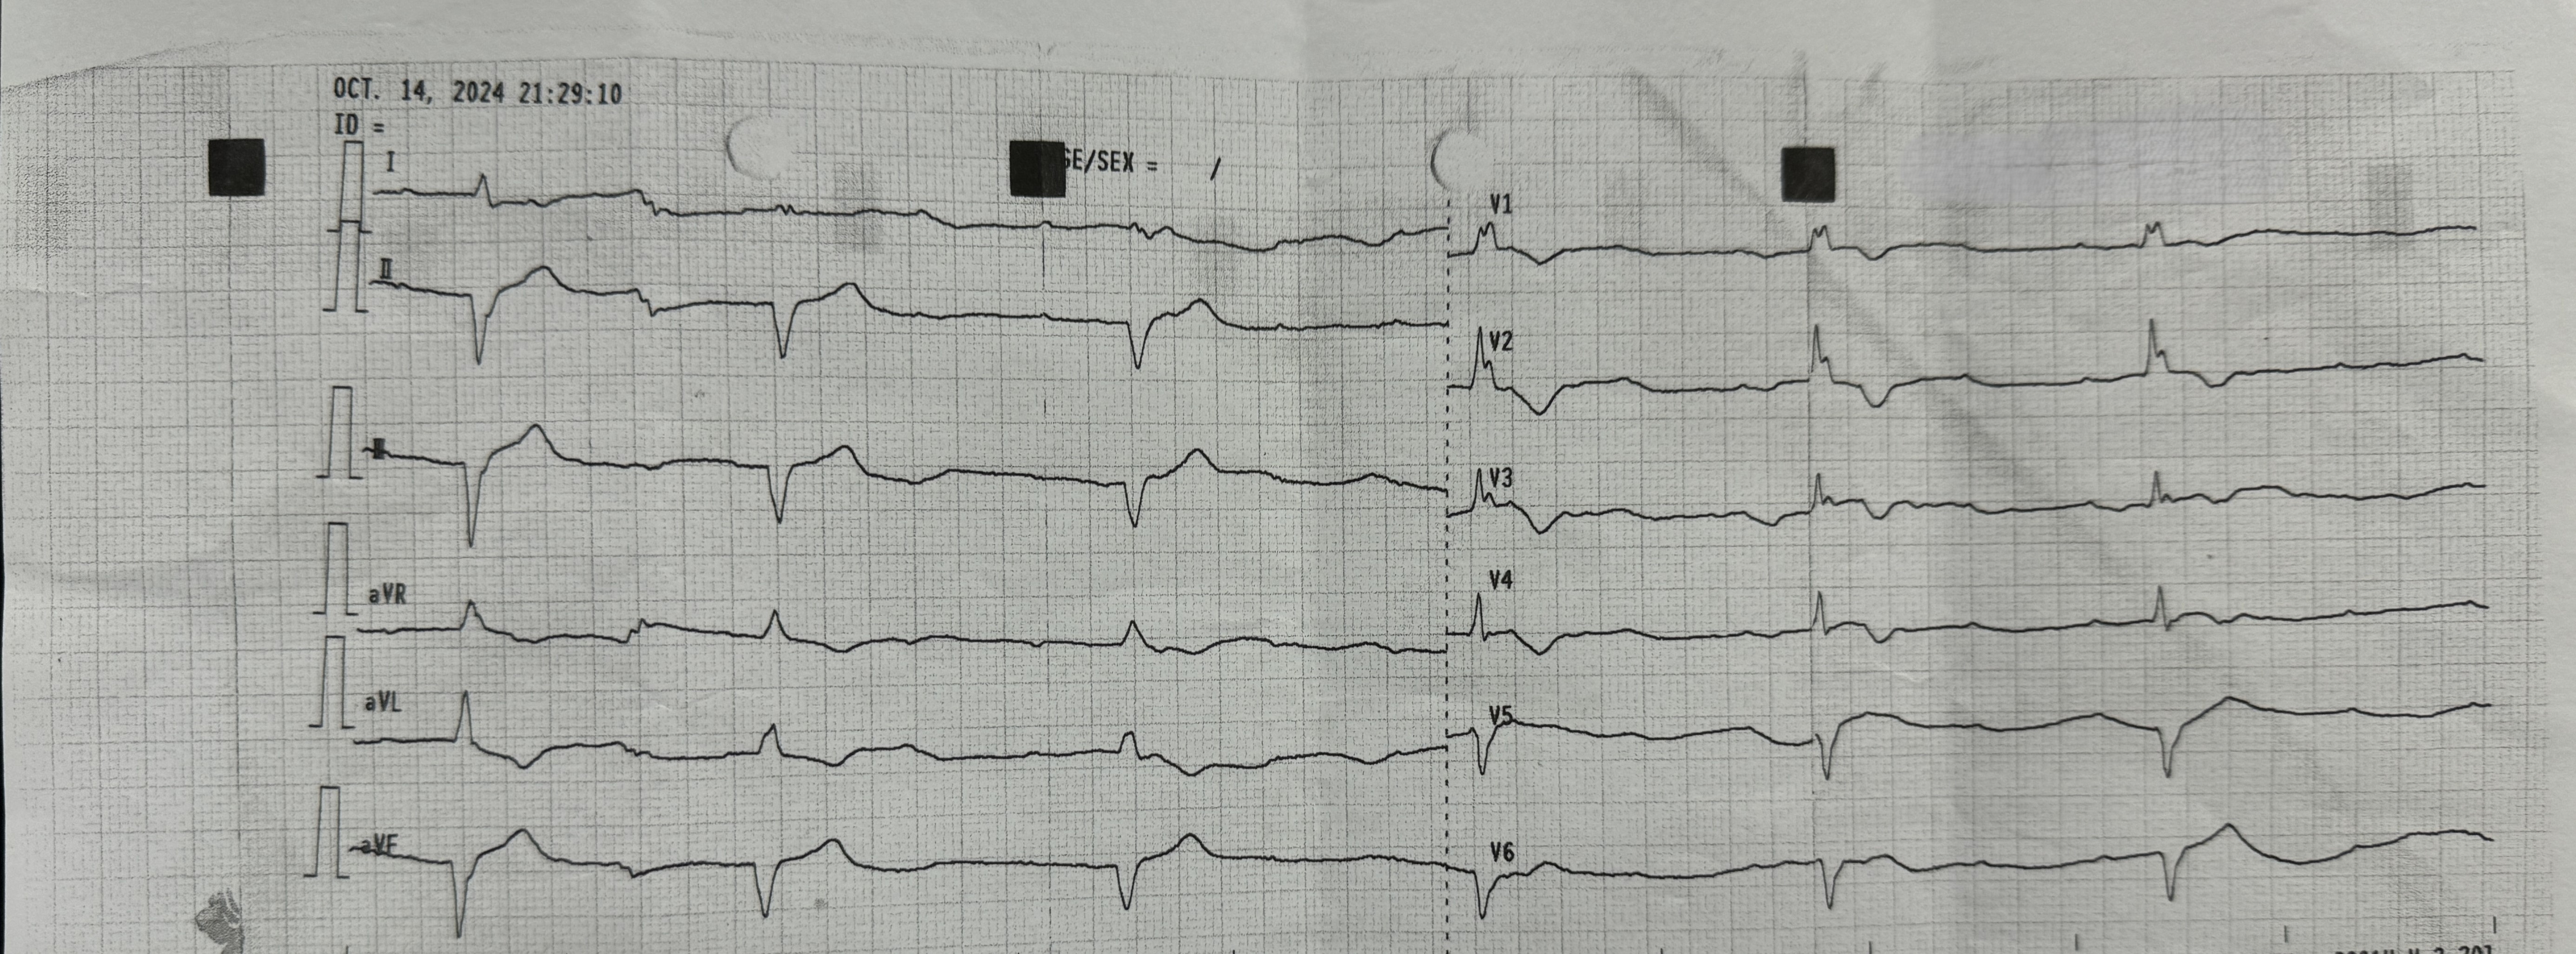

At the onset of chest pain, her electrocardiogram (ECG) showed total AV block and serial ECG showed QRS and ST-T changes. New onset Left Bundle Branch Block (LBBB) and ST-elevation was found in the inferior and anterior leads. Laboratory tests revealed elevated troponin levels consistent with acute STEMI and a positive IgM Salmonella Typhi (TUBEX) test.She had received a loading dose of dual antiplatelet therapy, fondaparinux, and ceftriaxone in the previous hospital.

Based on the clinical presentation, ECG, and laboratory results, the initial working diagnosis was Anterior STEMI with KILLIP Class IV. CAG was then performed via radial artery using a 6-French introducer sheath, revealing no significant stenosis in the coronary arteries. As the cardiogenic shock still persisted despite optimal inotrope and vasopressor, an IABP was then inserted via femoral artery with the initial setting of 1:2 assist ratio. She was then transferred to the intensive care unit (ICU) where bedside echocardiography revealed a left ventricular ejection fraction (LVEF) of 48% without regional wall motion abnormalities, supporting a non-ischemic etiology. During hospitalization the patient developed acute kidney injury (AKI) with anuria. Further workup for myocarditis showed elevated C-reactive protein (CRP), high procalcitonin levels, and metabolic acidosis. Blood culture was sterile as she had been given antibiotic before. Given rapid clinical deterioration, broad-spectrum antibiotics (meropenem and cefoperazone) were initiated, and hemodialysis was performed. Her condition steadily improved throughout treatment. The IABP was successfully weaned off after four days, and inotropes were gradually tapered off. Serial ECGs also showed gradual resolution of the ST segment elevation and LBBB. After ten days of optimal antibiotics treatment, she continued to improve and was safely discharged from the hospital.